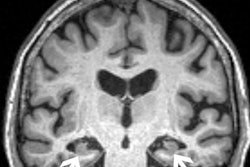

Heart and brain PET scans from a study participant who developed Parkinson’s disease support a “body first” progression. The top pair of PET scan images show low F-18 dopamine-derived radioactivity in the heart (right, with N-13 ammonia PET scan on left). Later, brain scans showed a loss of dopamine-producing neurons and the individual developed symptoms of the disease. Image courtesy of the National Institutes of Health.